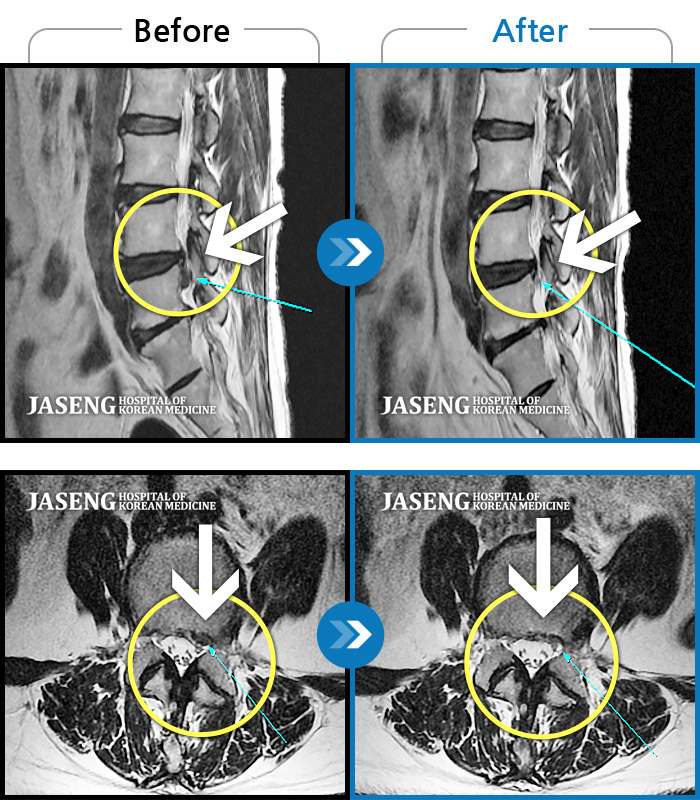

허리디스크

허리 통증 및 좌측 다리 마비 증상

촬영시기

2019.03.25 ~ 2019.11.04